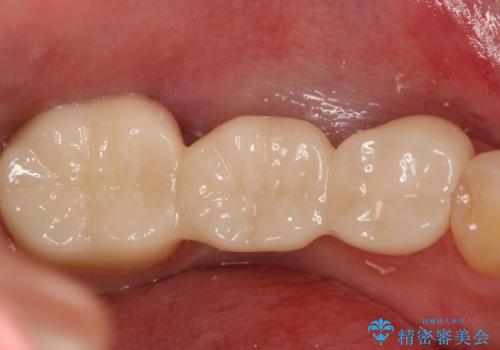

痛みは完全に取り除かれ、咬合時の違和感もなく経過は良好です。